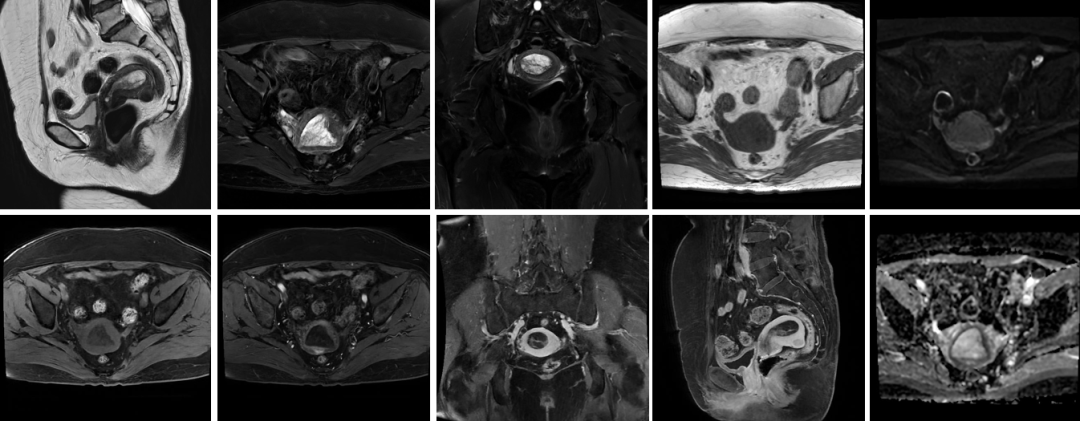

腹部盆腔:肝癌、胰腺癌、子宫肌瘤、前列腺癌、卵巢囊肿等;

盆 腔